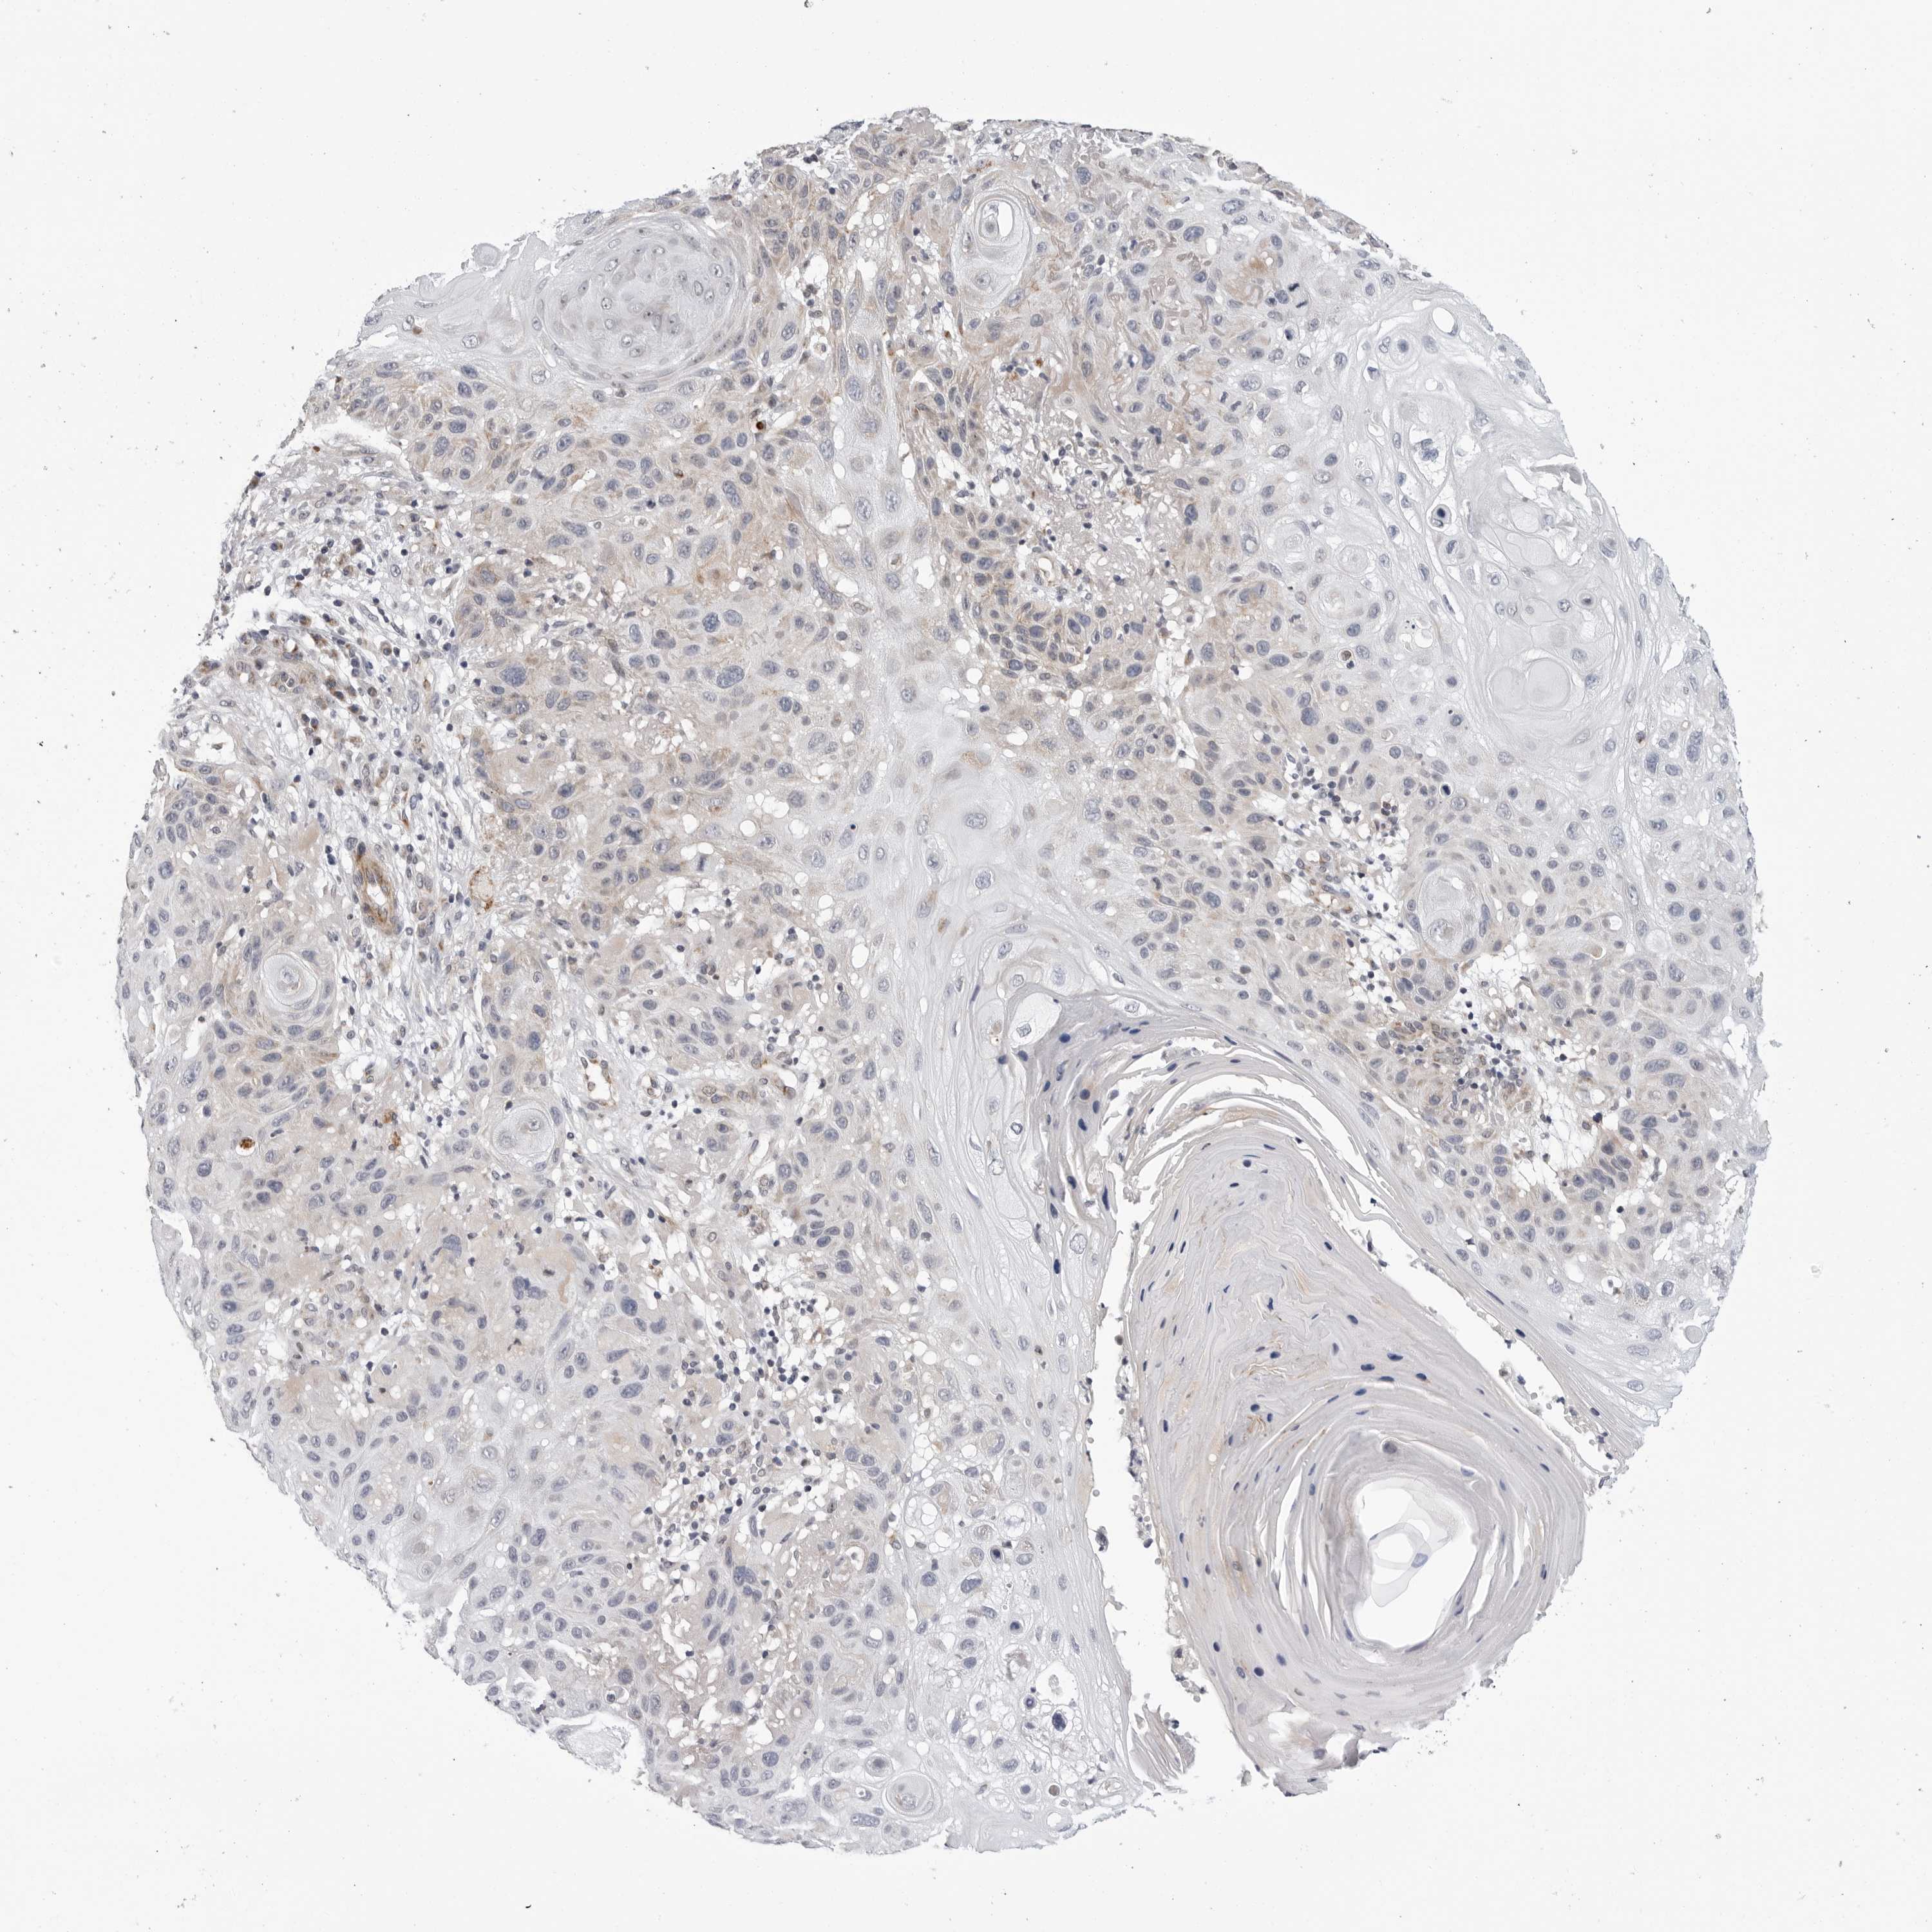

SKIN CANCER - Protein expressioni

A mouse-over function shows sample information and annotation data. Click on an image to view it in a full screen mode. Samples can be filtered based on level of antibody staining by selecting one or several of the following categories: high, medium, low and not detected. The assay and annotation is described here.

Antibody staining in the annotated cell types in the current human tissue is reported as not detected, low, medium, or high, based on conventional immunohistochemistry profiling in selected tissues. This score is based on the combination of the staining intensity and fraction of stained cells.

Each image is clickable and will lead to virtual microscopy that enables deeper exploration of all samples and also displays staining intensity scores, fraction scores and subcellular localization as well as patient and tissue information for each sample.

Antibody HPA007666

Basal cell carcinoma